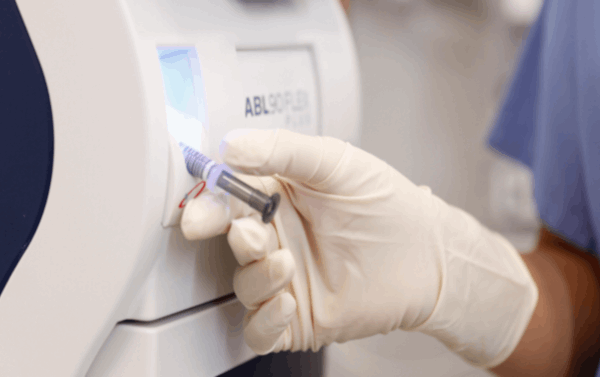

La gasometría arterial es una técnica médica fundamental que se utiliza para analizar el equilibrio ácido-base y evaluar la función respiratoria en pacientes. Consiste en la extracción de una muestra de sangre arterial, generalmente de la arteria radial en la muñeca o la arteria femoral en la ingle, para medir varios parámetros críticos.